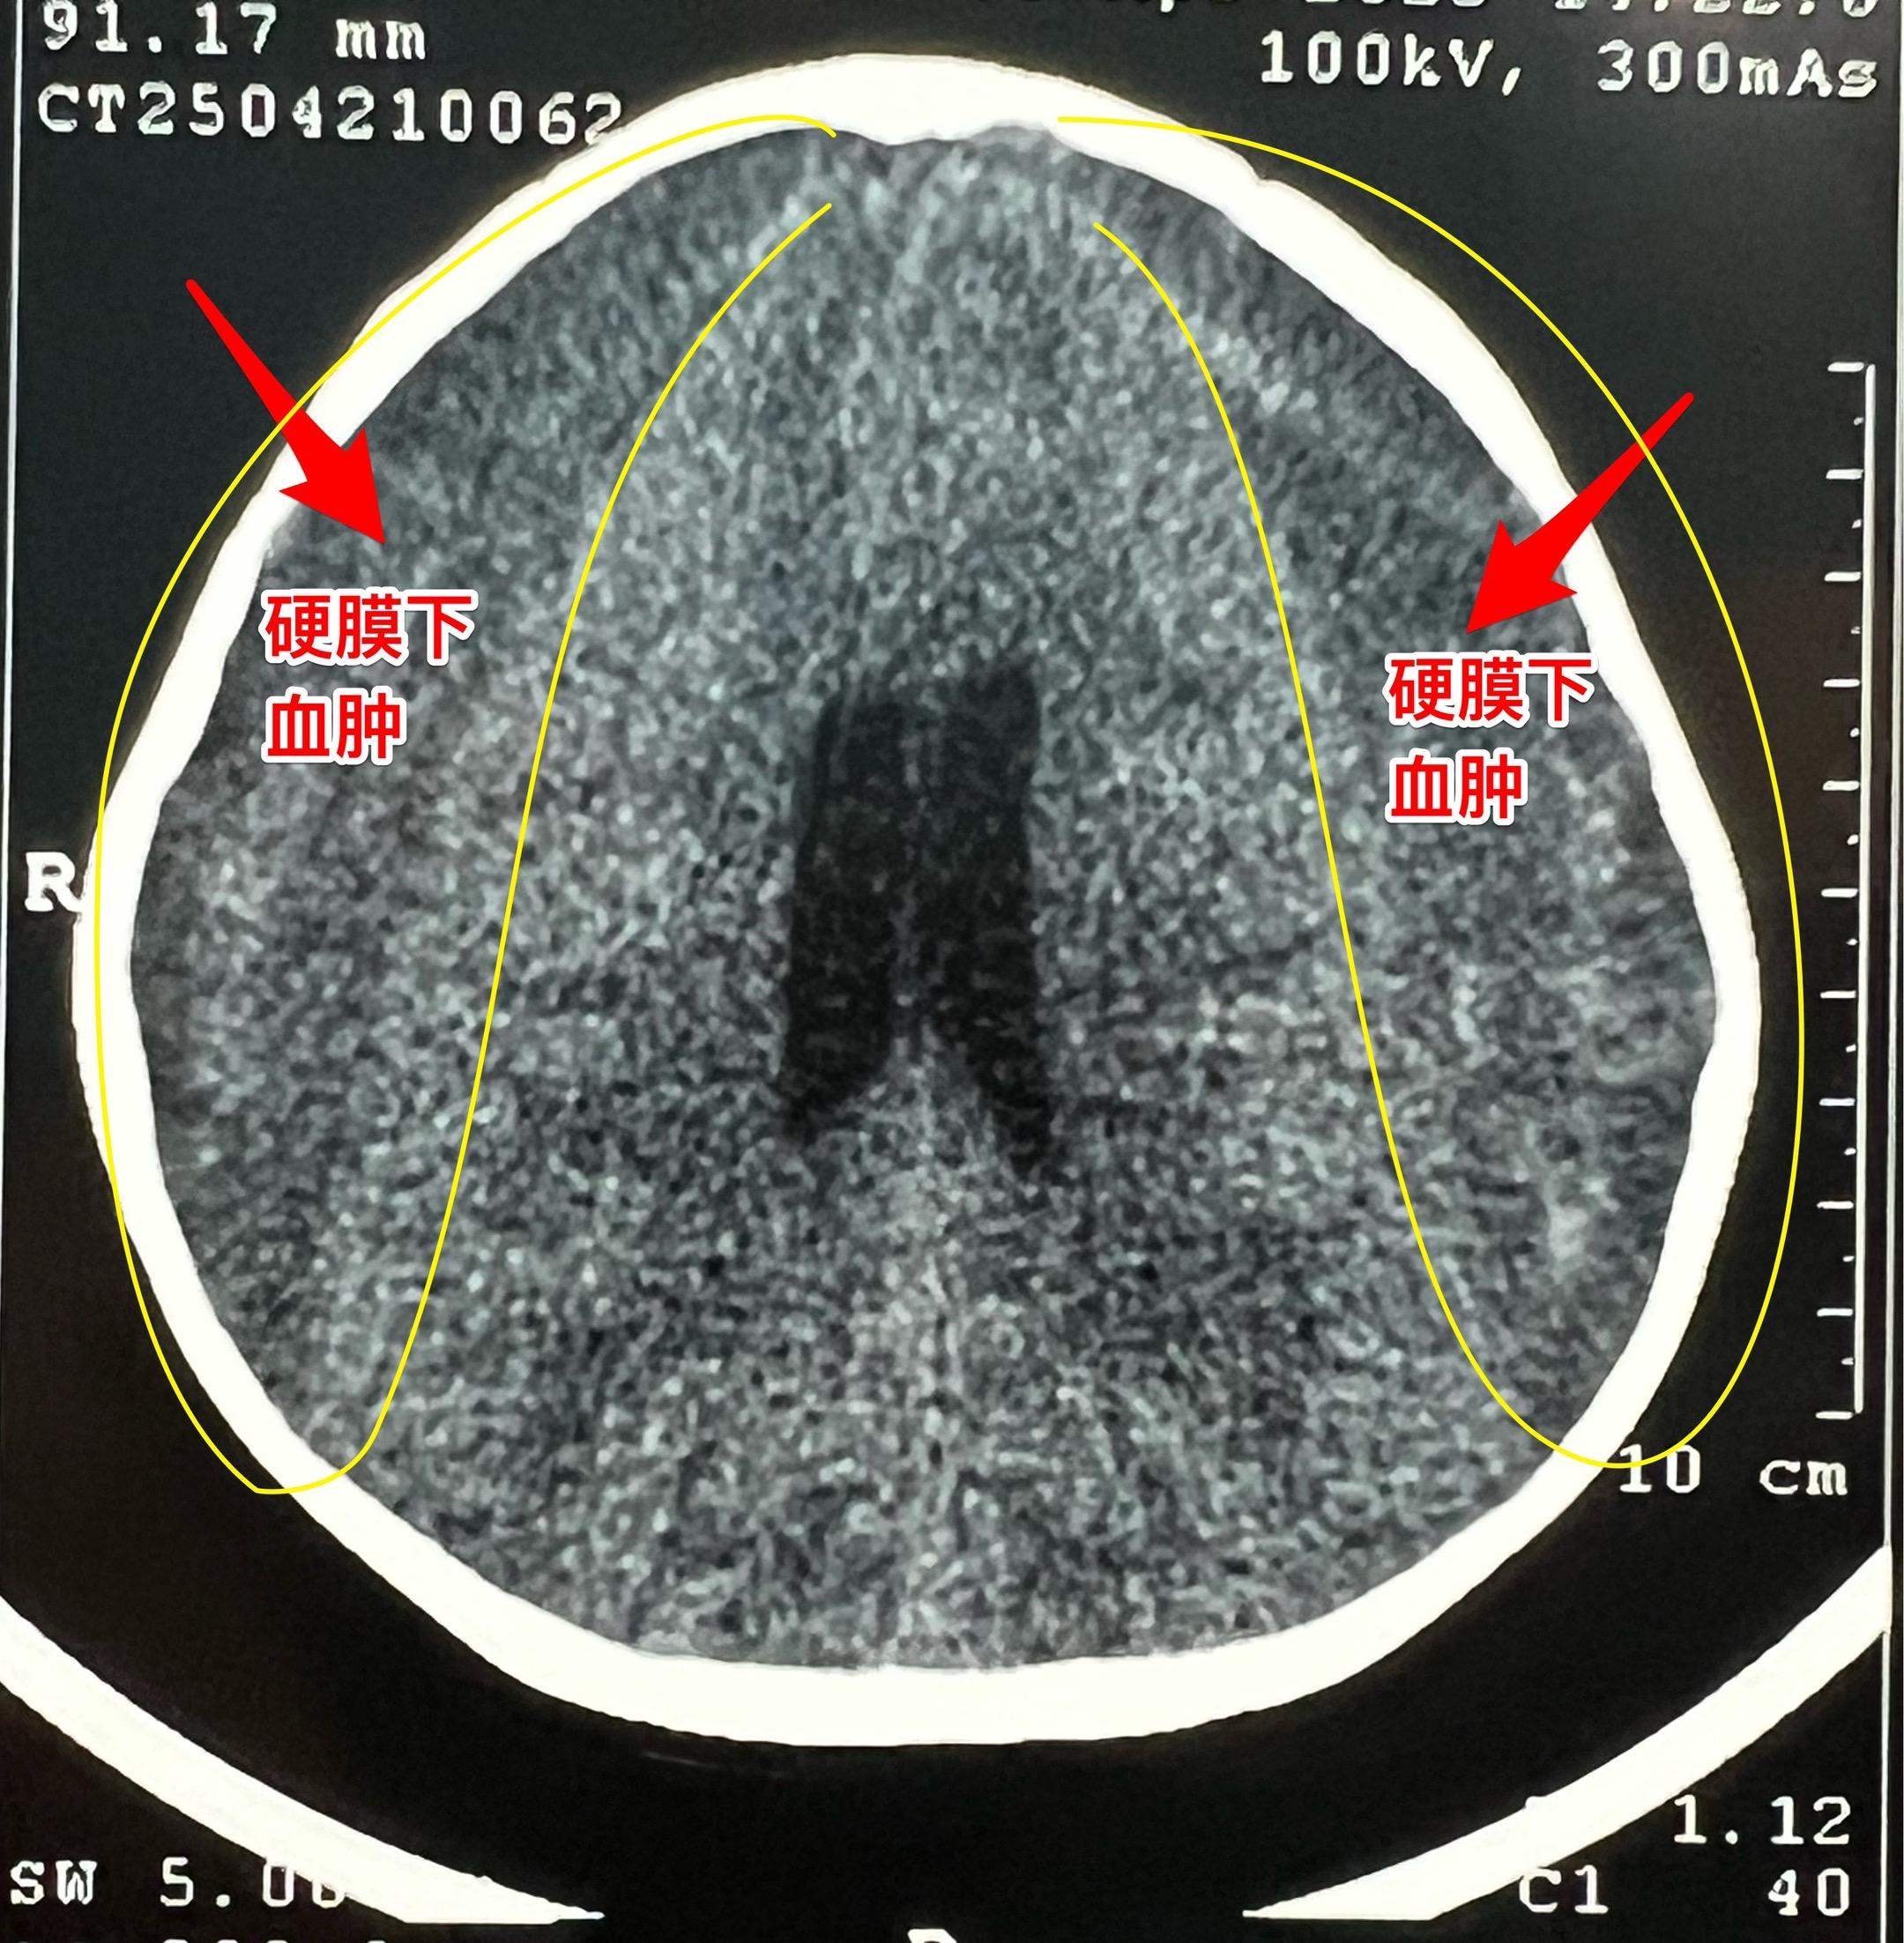

五岁男孩子双侧慢性硬膜下血肿。这个五岁男孩子,五个月前曾经在我科行颅咽管瘤切除手术。 颅咽管瘤切除后顺利出院。出院后三个月复查磁共振显示双侧脑部有硬膜下积液,逐步转为硬膜下血肿。小孩子没有头痛症状,家长发现小孩子行走步态不太正常,不像以前那样灵活。当时就打算给患儿作硬膜下血肿引流术。但是患儿因为感染病毒发烧,手术只好推迟。 4月25日给患儿作了硬膜下血肿引流手术。这个手术在我科属于很简单的手术。预计五一假期前就可以出院了。